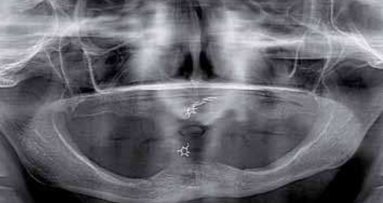

W fazie planowania leczenia wykonano badania OPG oraz CBCT. Badania uwidoczniły masywny zanik części zębodołowej wyrostka żuchwy do jej trzonu – klasa 3. Zanik ten nie wykluczał leczenia pacjentki, jednak eliminował żuchwę jako miejsce dawcze dla ewentualnych przeszczepów kości dla rehabilitacji szczeki. W szczęce uwidoczniono masywny zanik części zębodołowej wyrostka w odcinku przednim wraz ze zwiększeniem upowietrznienia zatok szczękowych i deformacją płaszczyzny powierzchni kości. Jest to obraz typowy dla pacjentów użytkujących przez lata protezy całkowite w szczęce przy współistniejącym uzębieniu resztkowym w odcinku międzybródkowym żuchwy. Taki stan nazywamy zespołem Kellego (Ryc. 1).

Taki stan jest ogromnym utrudnieniem dla leczenia protetycznego bezzębnej szczeki przez niekorzystną relację płaszczyzny pola podparcia protezy do płaszczyzny protetycznej. Znaczny stopień zaniku wyrostka w okolicy podnosowej eliminuje to miejsce z zabiegów GBR. Do rozważań pozostają zatem odcinki boczne w rzucie zatok szczękowych. W przypadku opisywanej pacjentki CBCT uwidoczniło zadowalający wymiar wertykalny przy ubytku horyzontalnym w postaci bagnetowatego szczytu wyrostka zębodołowego (Ryc. 2).

Po analizie CBCT z szablonem protetycznym zadecydowano o zastosowaniu metody augmentacji horyzontalnej z użyciem techniki śrub namiotowych w rzutach zatok szczękowych obustronnie. Jako materiał augmentacyjny postanowiono zastosować ksenograft (Bio-Oss) zmieszany z wiórami kości autogennej pobranej z otworów osteotomijnych w żuchwie.

Po kontroli dopasowania i kontroli okluzji uzupełnienie dokręcono z siłą 15 Ncm. Otwory śrub zamknięto kompozytem Luxaflow (DMG). Leczenie zostało zakończone (Ryc. 21-25). Efekt estetyczne w pełni zadowolił pacjentkę jak i zespół (Ryc. 26 i 27). Zlecono wizyty kontrolne co 6 miesięcy. Podczas kontroli przeprowadzonej 24 miesiące po oddaniu uzupełnień wykonano kontrolne CBCT, które ujawnia zadowalający stan podłoża kostnego (Ryc. 28-29).